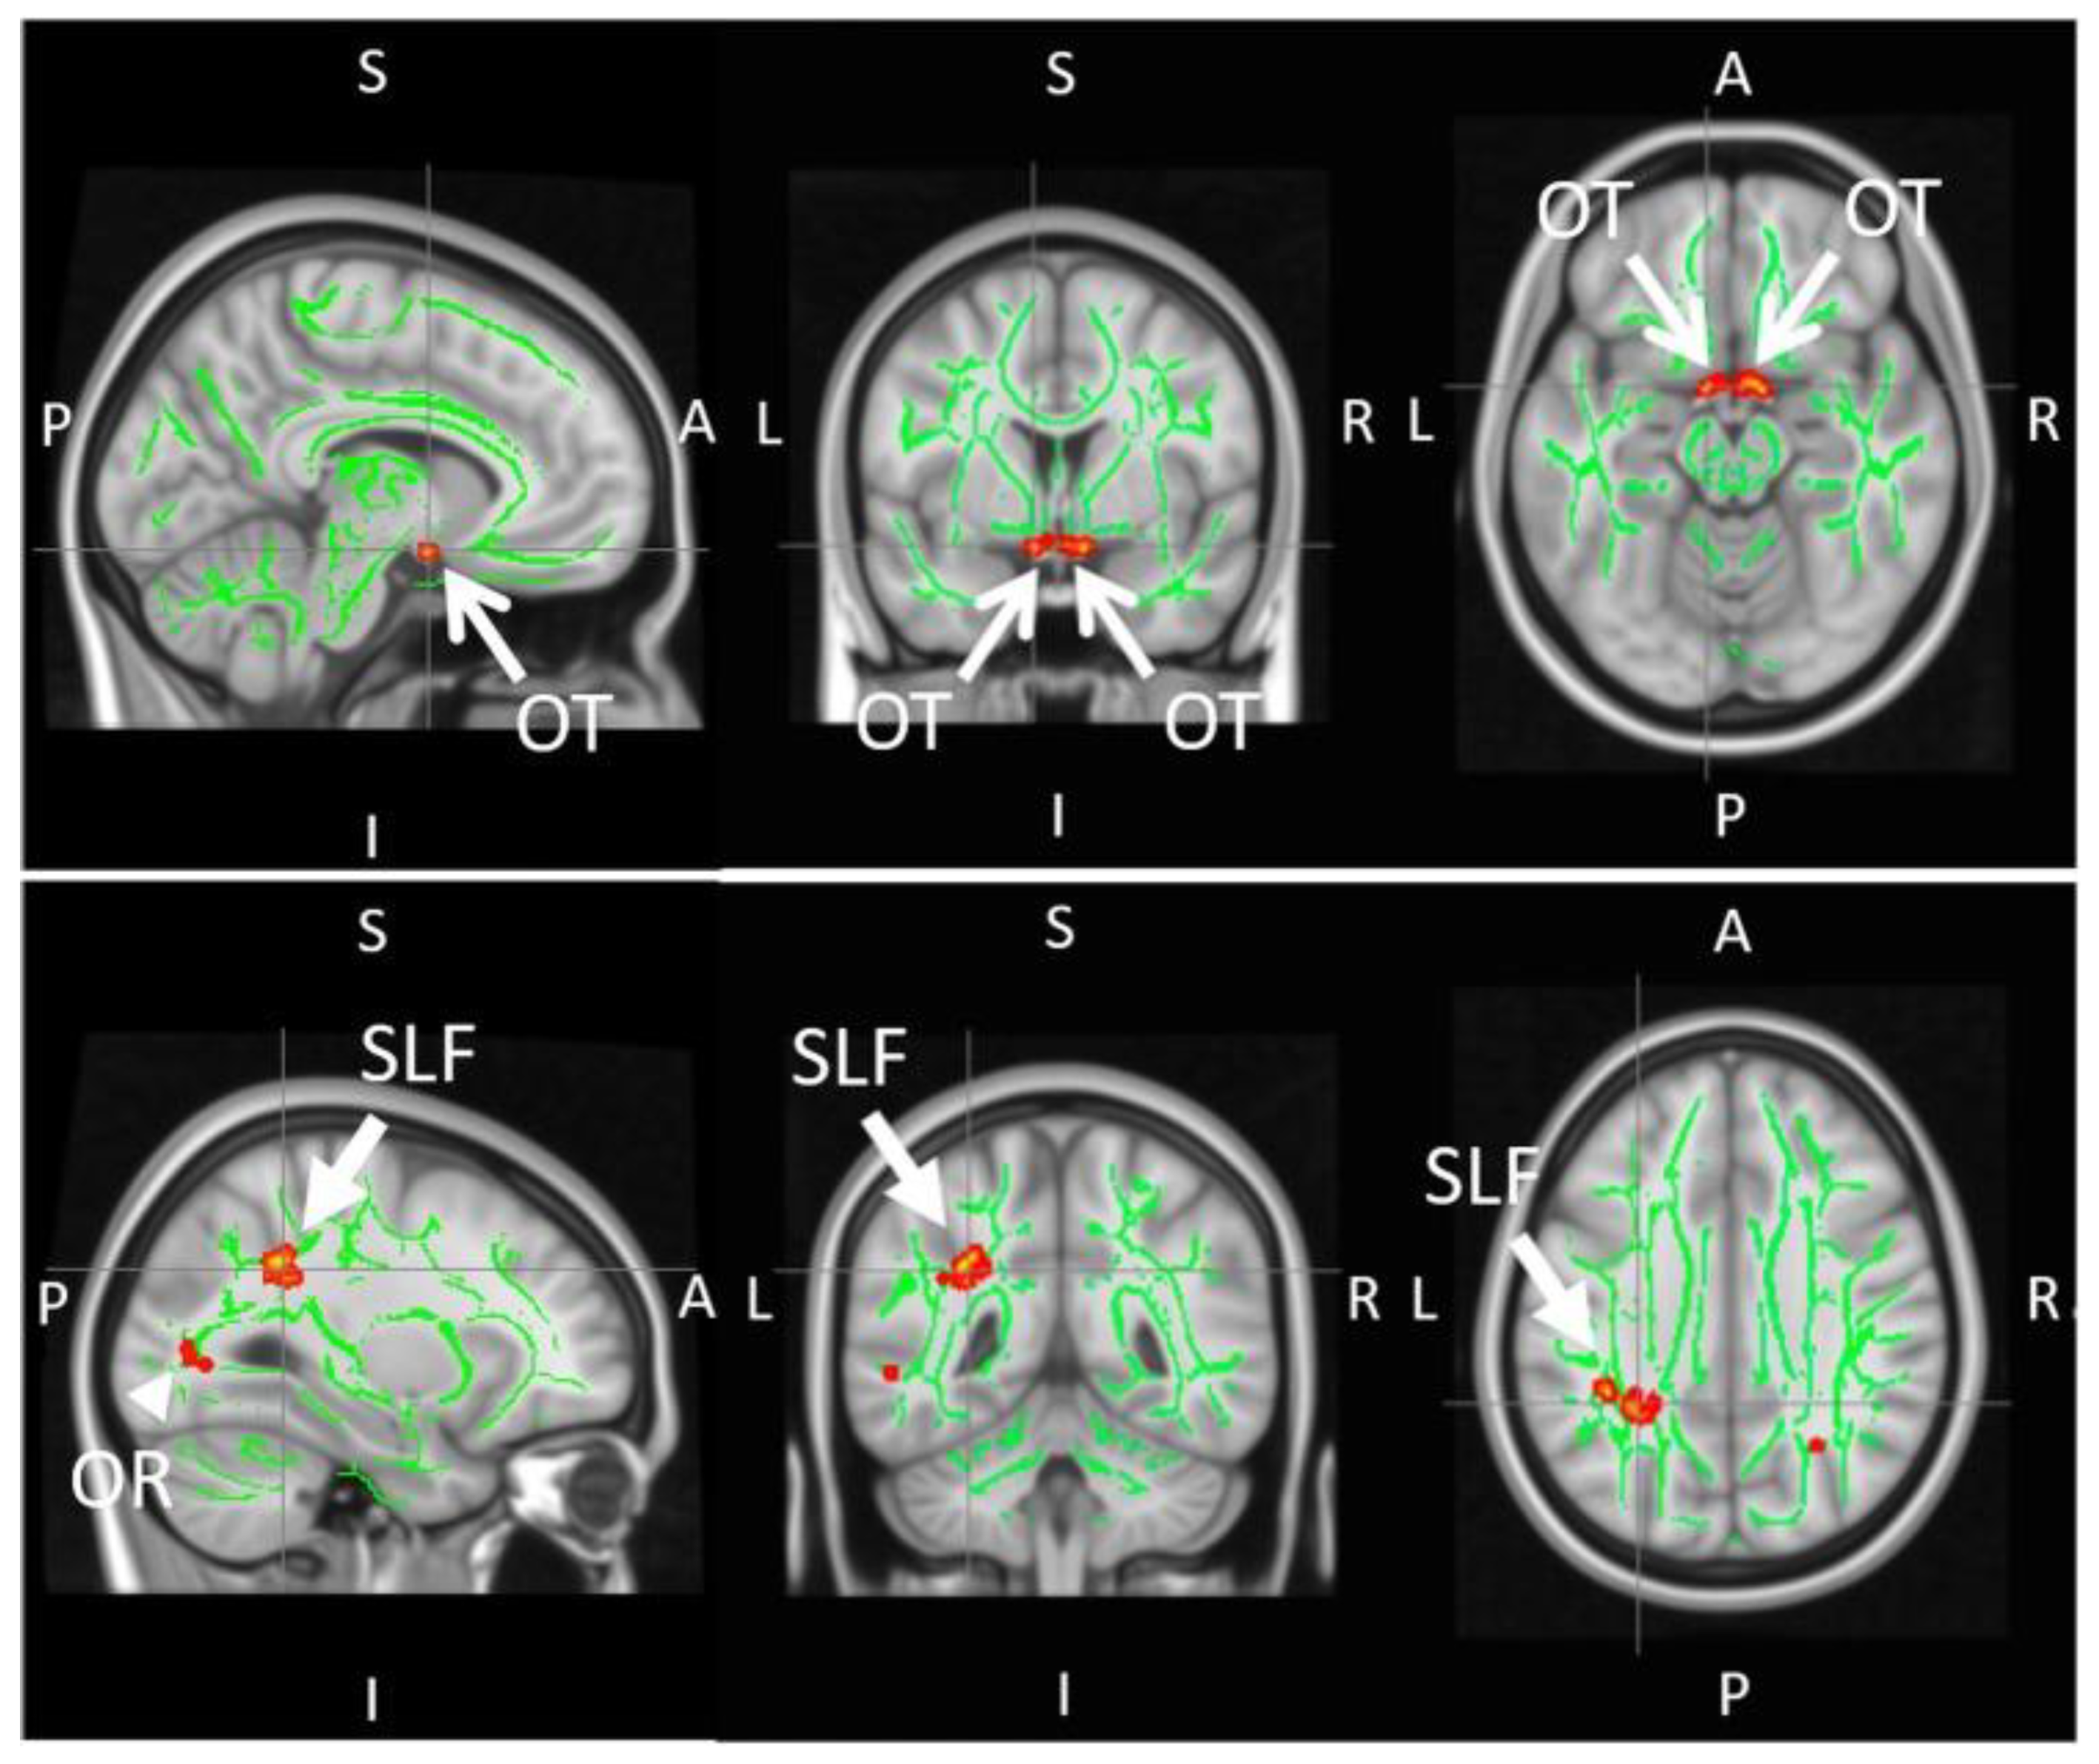

2.7. Diffusion MRI Tractography in Glaucoma